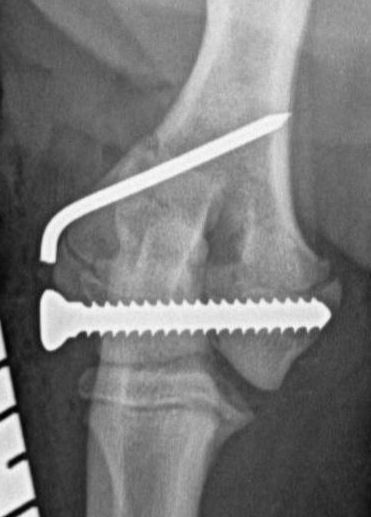

These concerns have led to recommendations being altered over the past decade or so, with veterinarians now using bone plates, instead of K-wires, as an adjunct to a transcondylar screw when managing humeral unicondylar fractures (Figure 2), even in puppies (Figure 3) (Clark, 2016; Kvale et al., 2022). However, the basis on which this conclusion for puppies was reached appears to have been flawed because it assumed that what had been shown to be the case for adults would also apply to immature patients. As the conclusion was felt to conflict with the author’s experience of treating such patients, a retrospective study was undertaken to evaluate complications and outcomes in immature dogs treated for humeral unicondylar fractures at one centre over a 10-year period (Butterworth, 2022). The findings of this study are summarised in this article.

Therefore, if the current trend towards the use of epicondylar plates, rather than K-wires/pins, in combination with a transcondylar bone screw to manage humeral unicondylar fractures in adults is also adopted for skeletally immature patients, we might well be throwing the puppy out with the bath water. The exception might be when the epicondylar ridge shows comminution, which means that a single K-wire might not provide enough stability, or when the patient shows prodromal lameness (both of which were noted in the patient related to Figure 3).